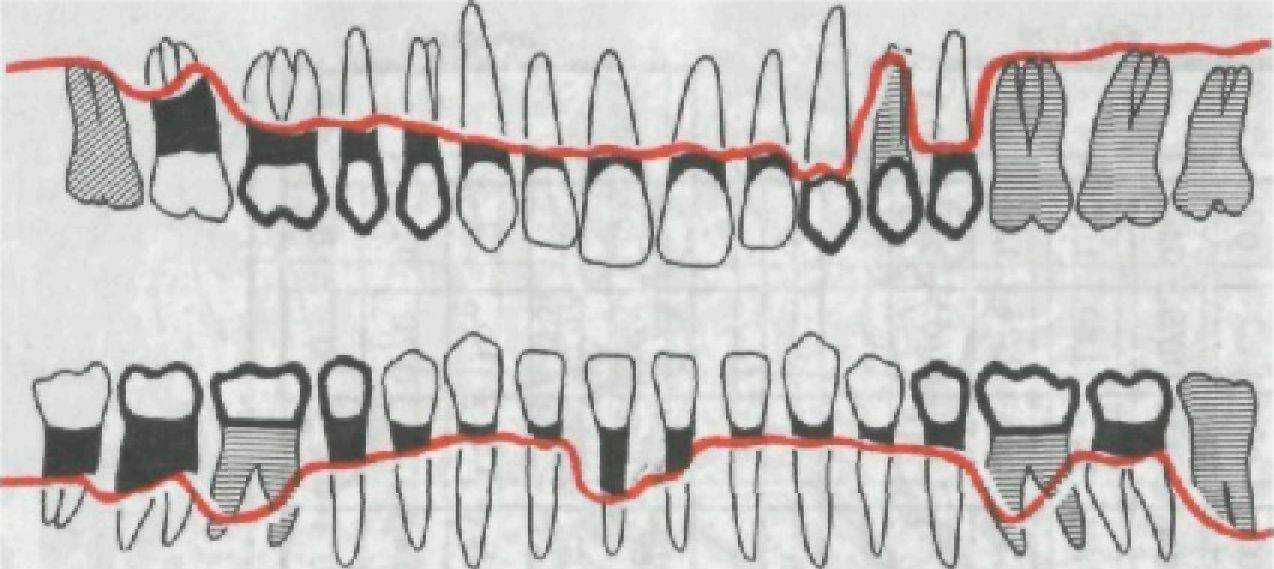

Для записи данных о глубине патологического кармана В. Ю. Курляндский предложил одонтопародонтограмму (рис. 150). В графы этой схемы-чертежа вносят результаты измерений каждого зуба (наибольшая глубина кармана без указания стороны, где локализованы большие изменения). К глубине кармана прибавляют величину обнажения корней зубов («видимая атрофия»). В. Ю. Курляндский различает четыре степени атрофии.

Степень атрофии пародонта и функциональная ценность зубов лежат в основе выбора метода лечения пародонтита. Пародонтограмма приобретает особое значение при повторных обследованиях, позволяя путем сопоставлений судить о динамике процесса и результатах лечения.

Предложены и другие методы записи степени резорбции костной ткани стенок альвеол (рис. 151).

Рис. 151. Вариант графической записи степени резорбции костной ткани стенок альвеол.